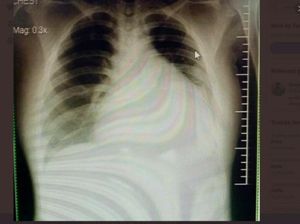

Viral Kisah Pasien Muda Kena Gagal Ginjal-Jantung Gegara Suka Minum Manis

Kisah pasien usia 20-an mengalami gagal ginjal akibat kebiasaan buruk sering mengonsumsi minuman manis viral di media sosial. Bagaimana ceritanya?